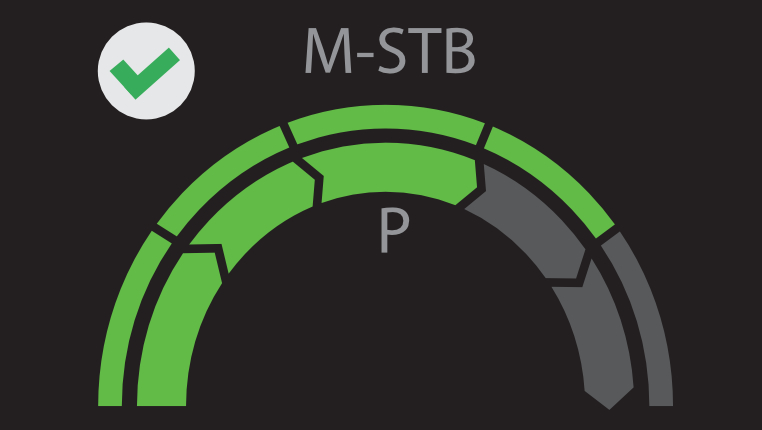

VÃĄrias solu??es de ultrassom*

â Sonda de ultrassom profissional para facilitar o exame de ascite, etc.

â Pun??o guiada por ultrassom dedicado para aprimorar a precis?o das biÃģpsias

â A excelente qualidade de imagem e as fun??es de ultrassom permitem uma avalia??o abrangente da morfologia e hemodin?mica do fÃgado.

â Pun??o guiada por ultrassom dedicado para aprimorar a precis?o das biÃģpsias

â A excelente qualidade de imagem e as fun??es de ultrassom permitem uma avalia??o abrangente da morfologia e hemodin?mica do fÃgado.

* DisponÃvel no Hepatus 6